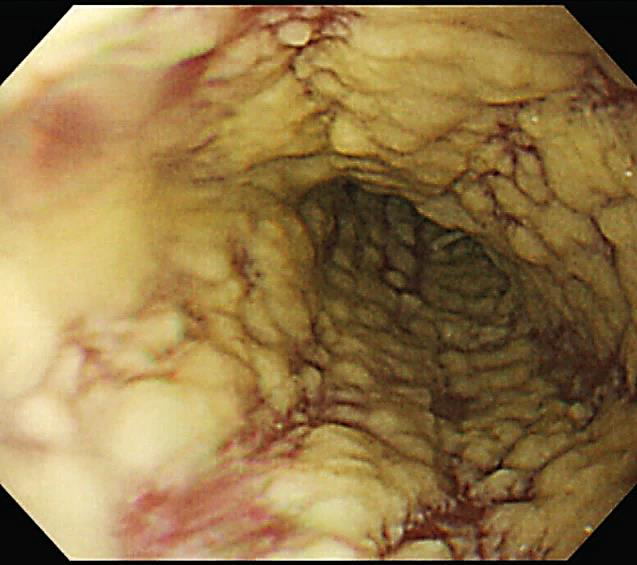

Homem, 27 anos, sem comorbidades prévias conhecidas, iniciou quadro de disfagia alta há dois meses, episódios de febre ocasional não aferida e perda de 4 Kg, a qual relacionou à dificuldade de se alimentar. Conta ainda que nos últimos cinco dias vem sentindo discreta dispneia ao caminhar e dor torácica ventilatório dependente em hemitórax direito. A febre tornou-se mais intensa e diária, atualmente aferida em 38,5 a 39°C, além de tosse produtiva com secreção amarelada e sem hemoptise. Ao exame físico, regular estado geral, presença de estertores crepitantes em base pulmonar direita. Frequência respiratória de 25 incursões por minuto, saturação de oxigênio 95%, frequência cardíaca 98 batimentos por minuto, pressão arterial 110/80 mmHg e perfusão preservada. Oroscopia, abdome, neurológico e de membros inferiores sem alterações dignas de nota. Foram solicitados os exames de investigação descritos abaixo (Figuras 6 e 7):

----------------------------------------------Figura 7. Endoscopia digestiva alta

Assinale a alternativa que apresenta qual a melhor conduta neste momento.